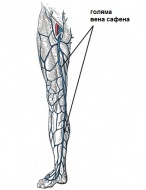

S85.3 Травма на vena saphena magna на ниво подбедрица

Vena saphena magna е разположена повърхностно по подбедрицата, точно под слоевете на кожата. Тъй кат...

S85.4 Травма на малката vena saphena на ниво подбедрица

Малката vena saphena е сравнително голям венозен съд, който се намира по задната повърхност на подбе...